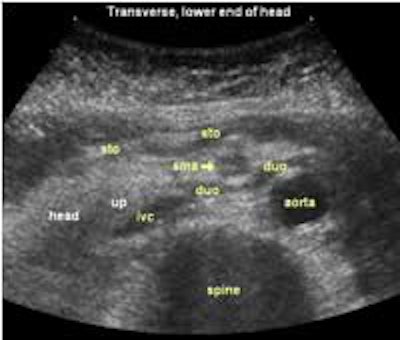

The following study describes anatomical landmarks in the ordinary pancreas of a thin patient:

Transverse planes in caudal direction: